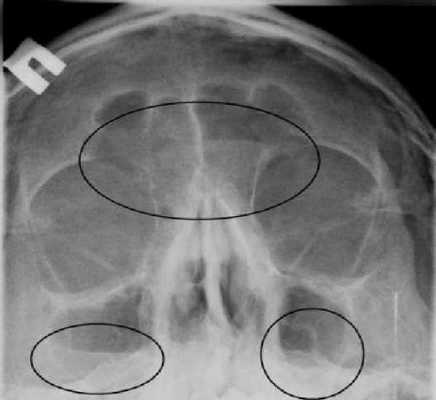

Фото снимка здорового человека

Теменно-акантиальная проекция (по уотерсу)

Для визуализации костей лицевой части черепа необходимо отвести изображения каменистых пирамид от лицевых костей. Это можно сделать или с помощью наклона ЦЛ, или разгибания шеи. На рентгенограммах справа (рис. 12-37 и 12-38) показан результат. Подбородок пациента поднят таким образом, чтобы каменистые пирамиды проецировались сразу ниже верхнечелюстных пазух. Центральный луч параллелен подборо-дочно-ушной линии (ПУЛ). Рентгенограмма справа (по Уотерсу, рис. 12-38), при правильно выполненной укладке, описание которой будет приведено далее в настоящей главе, демонстрирует каменистые пирамиды (см. стрелки), спроецированные ниже верхних челюстей и верхнечелюстных пазух. Таким образом, за исключением нижней челюсти, кости лицевого черепа проецируются выше плотных каменистых пирамид, и изображения последних не налагаются на кости лицевого черепа.

В норме при рентгенологическом исследовании содержащие воздух ОНП выглядят, как светлые участки с чётко обозначенным тёмным контуром, соответствующим их костной границе. Обычно описывают негативное рентгеновское изображение, поэтому более тёмными называются участки, содержащие больше белого цвета. Пневматизированные ОНП соответствуют прозрачности орбит. Если содержимое пазух темнее содержимого орбит, то говорят о затемнении, которое означает наличие патологического процесса. При этом нужно охарактеризовать затемнение по нескольким параметрам. Первый из них - размер или степень заполнения пазухи патологическим процессом.